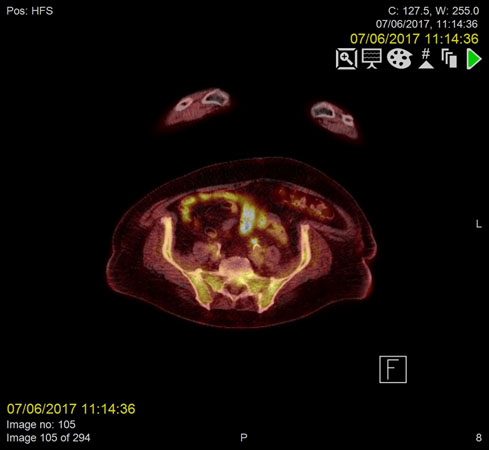

F18-FDG PET images were acquired from the skull base to the mid-thighs together with low dose CT for attenuation correction and anatomical co-location. This showed no malignancy but demonstrated high activity at the sites of the thrombus within the confluence of the SMV and portal vein as well as the distal IMV, in keeping with infected thrombi.

Repeat F18-FDG PET- CT images acquired two months later demonstrated complete resolution of the IMV and SMV thrombi (Figure 1-2).

Figure 1a. Metabolically active, infected thrombus in Inferior mesenteric vein (IMV) demonstrating increased FDG uptake on PET/CT prior to anticoagulant treatment